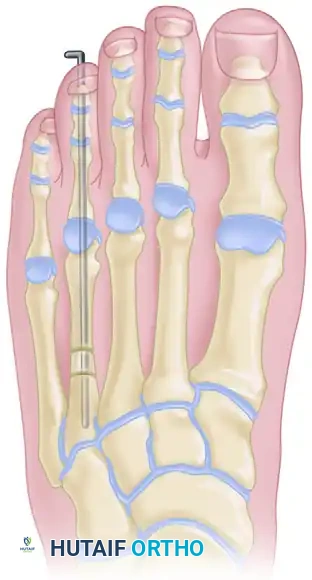

One-Stage Lengthening with Interpositional Graft

One-stage lengthening is generally reserved for mild deformities where the required lengthening is less than 10 to 15 mm. Attempting acute lengthening beyond this threshold places excessive tension on the neurovascular bundles, risking digital ischemia and severe soft tissue contracture.

Figure 8: Lengthening of the metatarsal utilizing a one-stage allograft interposition technique. Rigid internal fixation (typically with a plate or intramedullary K-wire) is required to stabilize the intercalary graft.